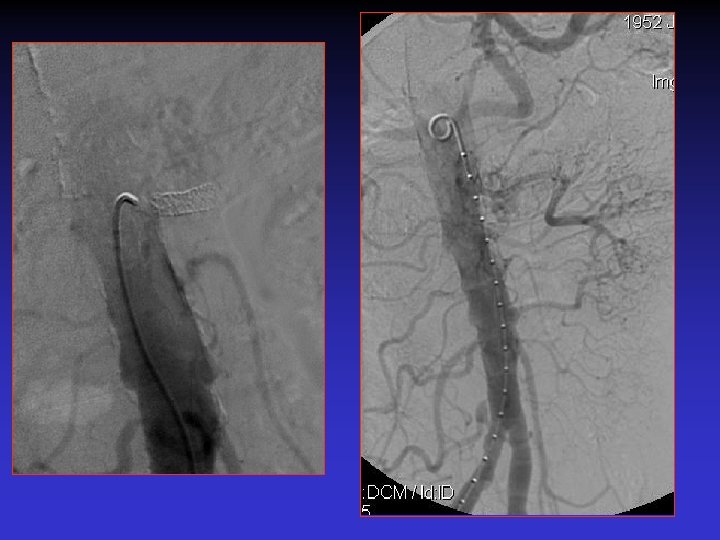

Case #1 S/p EVAR new onset of HTN

Case # 2 • 50 -year-old male with solitary kidney. • Smoker. • Refractory HTN. • Cr: 3. 8 mg/dl

• B/P: 160/80 mm. Hg • Cr: 1. 8 mg/dl